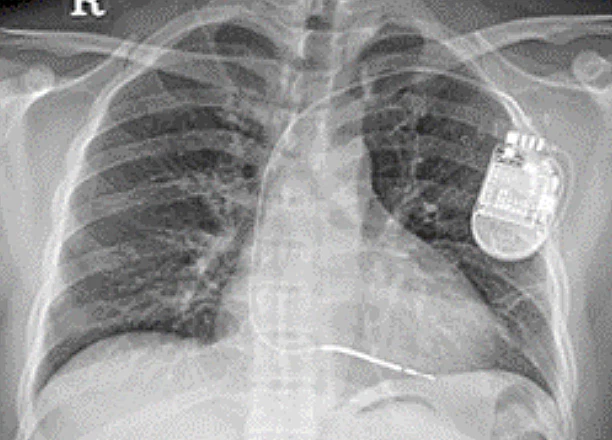

이식형 제세동기란?(자동제세동기 ICD, Implantable Cardiac Defibrillator)

심정지를 일으킬 수 있는 치명적인 부정맥이 발생했을 때 부정맥을 종료시키고 정상 리듬으로 돌려주는 기계입니다.

부정맥에 의한 급사 위험이 있는 환자에게 이식하고 인공심박동기와 같은 기능도 있어서 심정지나 서맥이 발생하면 정상 맥박수로 뛸 수 있도록 조율 가능합니다.